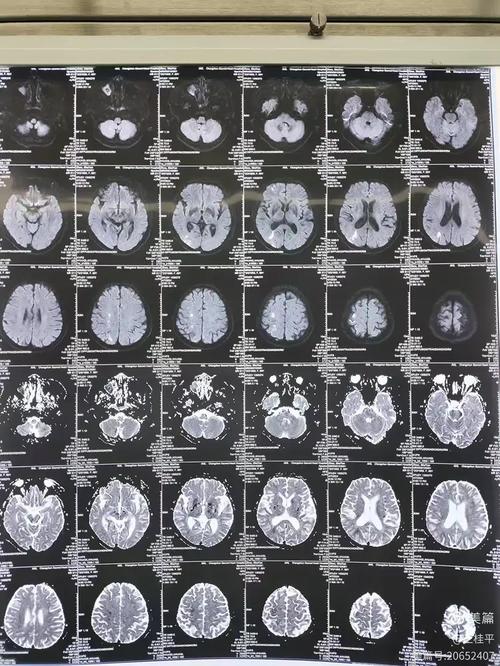

- 头颅MRI+DWI+MRA/CTA: MRI是发现脑梗病灶最敏感的检查,MRA(磁共振血管成像)或CTA(CT血管成像)可以查看脑血管有无狭窄或闭塞。